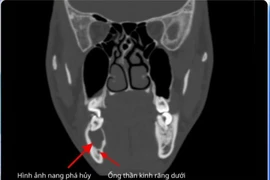

Đi khám sức khỏe phát hiện ung thư amidan

Người dân cần chủ động thăm khám sức khỏe định kỳ, đặc biệt khi có dấu hiệu bất thường vùng tai mũi họng, đau họng kéo dài, nuốt vướng, khàn tiếng, nổi hạch cổ…